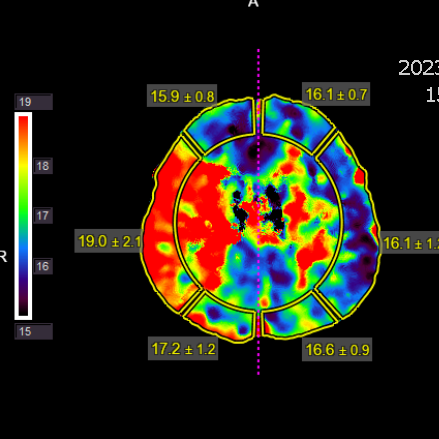

复查脑灌注相对缺血比术后1.5个月有加重

灌注比术前进一步改善